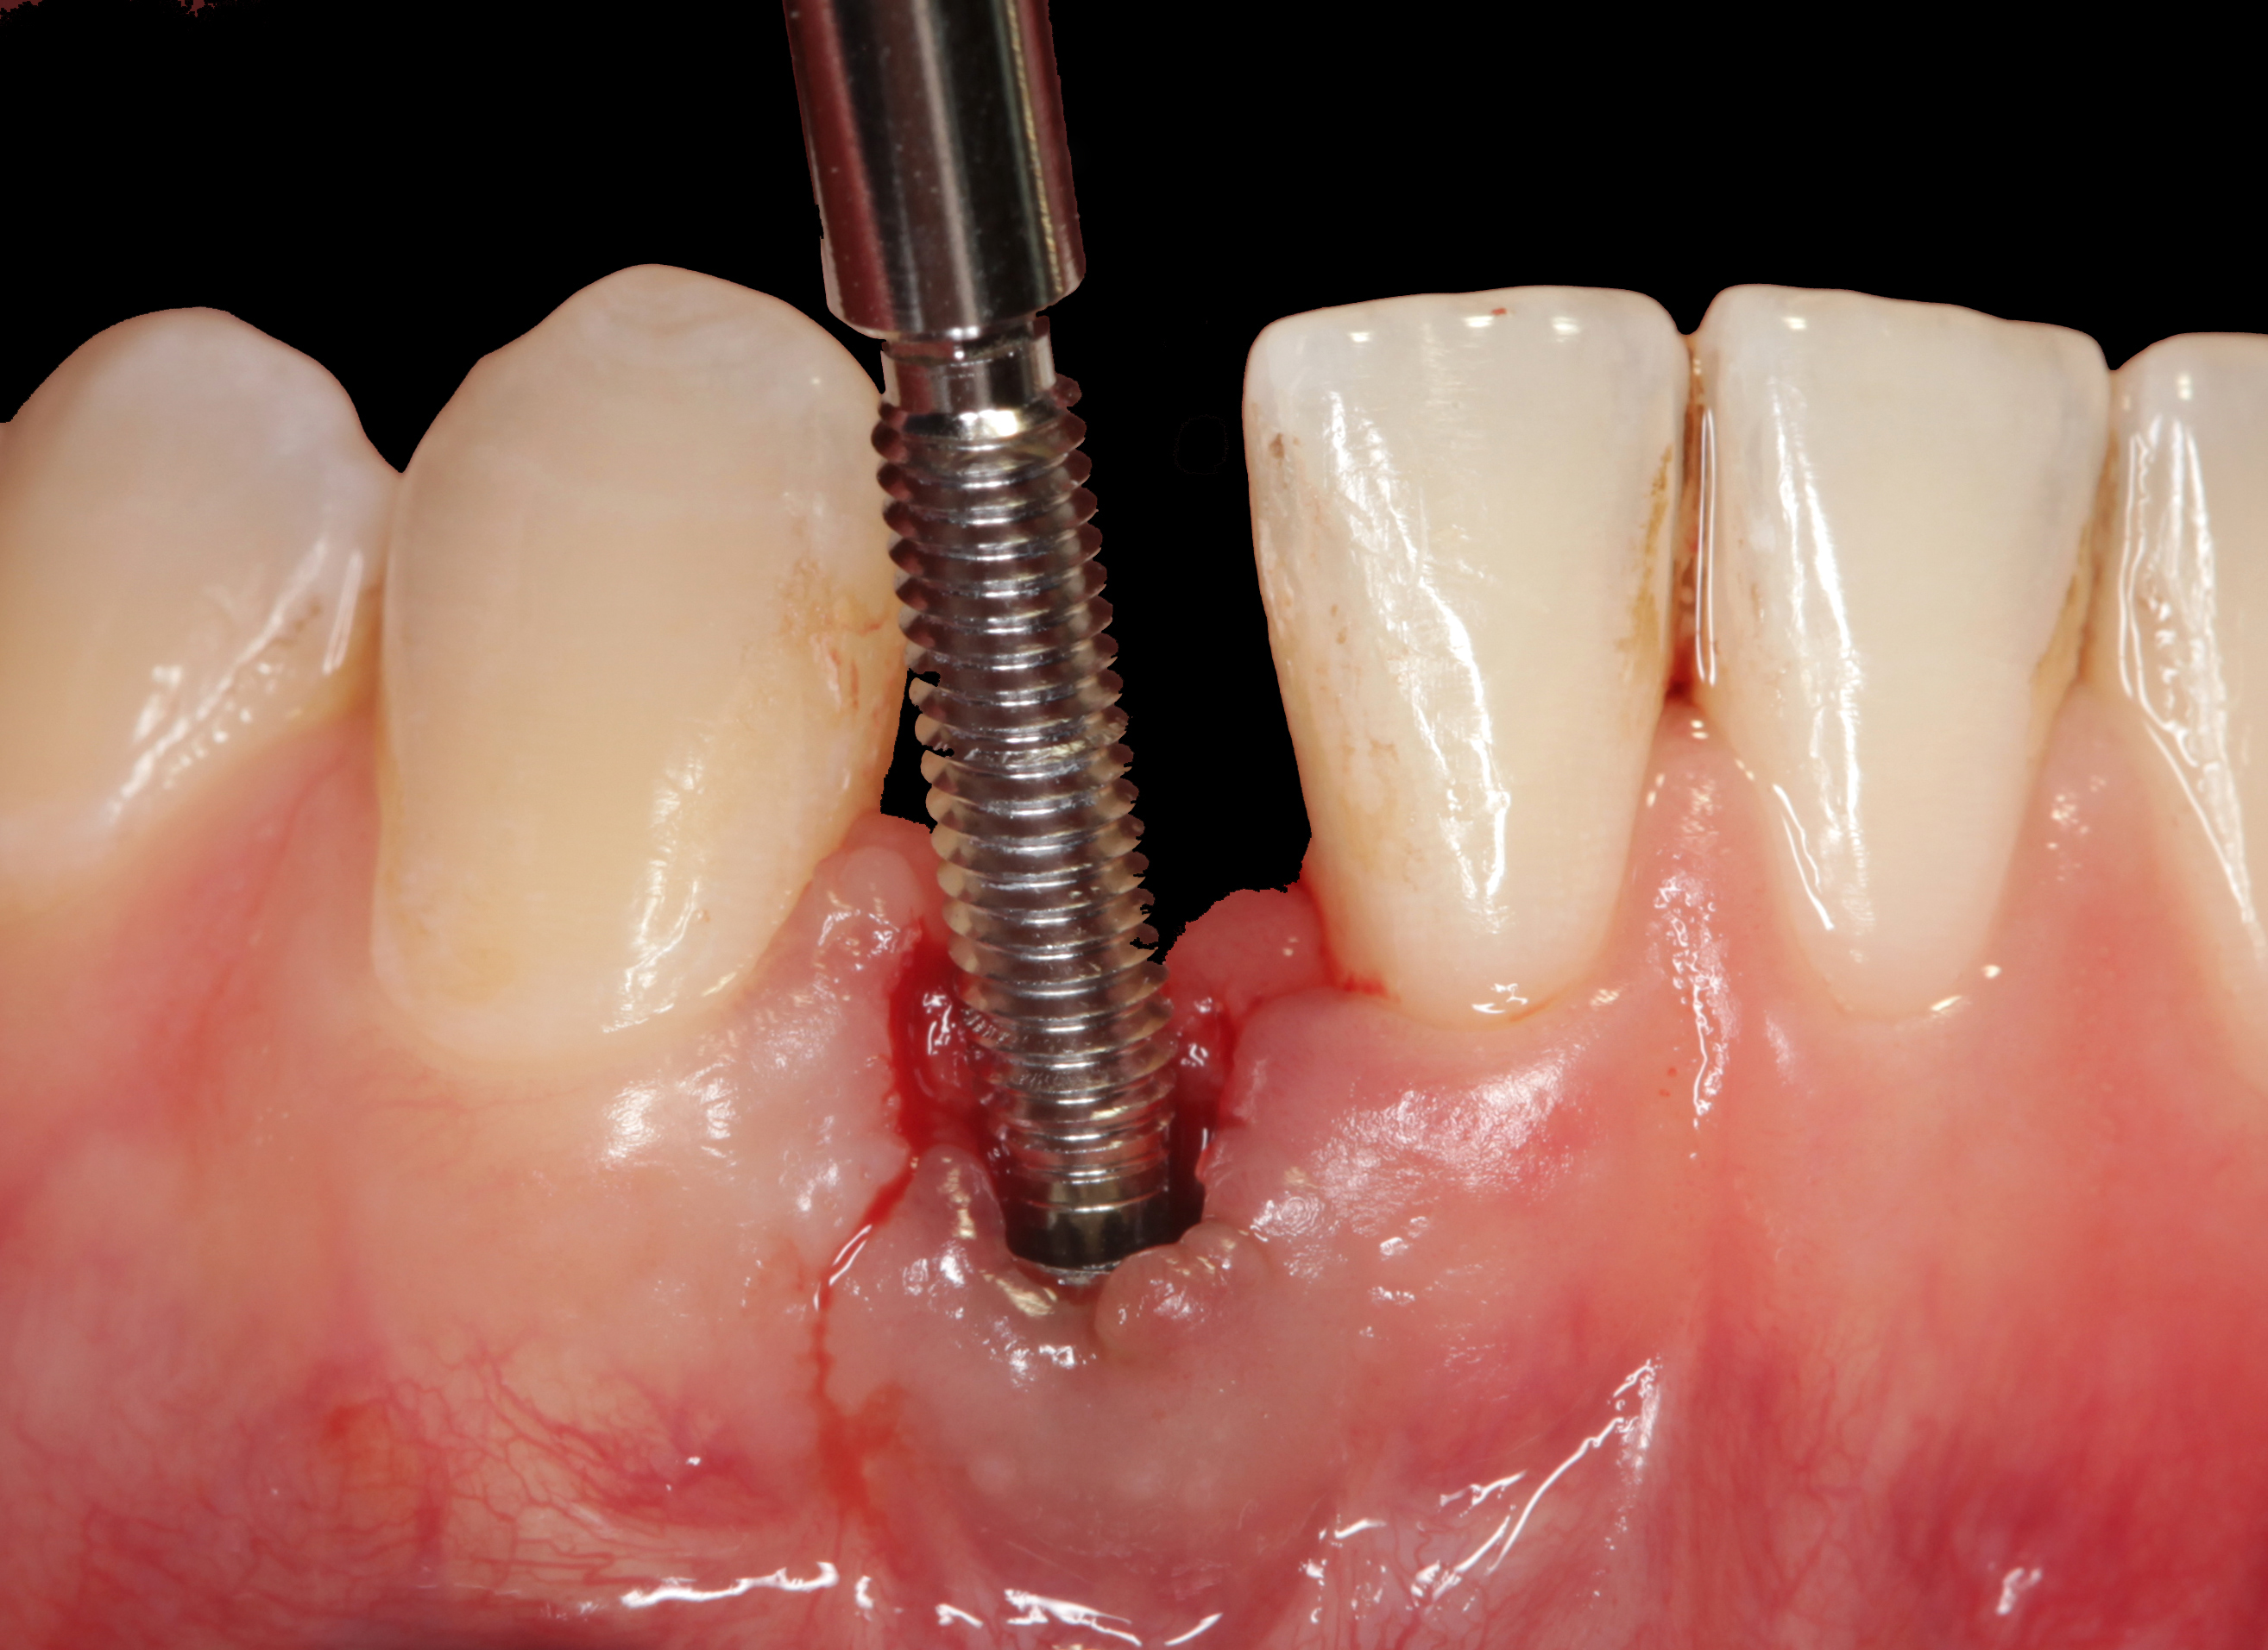

The crown and screw-retained custom abutment were removed, and a surgical cover screw was placed into the implant, thereby allowing spontaneous gingival augmentation in situ (Figure 33 and Figure 34). Note that the lingual aspect of the implant site was significantly more coronal than the labial aspect, which was positive because the defect would be limited to a facial–lingual defect. A fixed RBR bridge was cemented on the adjacent teeth and used as a tooth-supported transitional provisional restoration (Figure 35). A few weeks were allotted to let the soft tissue heal and migrate around the cover screw (Figure 36) to see if there would be complete coverage, thereby allowing a soft-tissue augmentation procedure to be performed with primary flap closure as in clinical scenario No. 2. The major obstacle in achieving a positive tissue response was that the implant depth was also deficient because the implant–abutment connection was at the level of the free gingival margin. It was decided that the best treatment option would be to remove the implant. A high-powered reverse-torque device (Fixture Remover Kit, NeoBiotech, www.neobiotechus.com) was used to remove the implant atraumatically (Figure 38 through Figure 41). The implant socket was allowed to heal for several months not unlike an extracted tooth (Figure 42). A new implant was placed in a better position from both a restorative and esthetic perspective (Figure 43), and after a few months of healing, a new crown was made (Figure 44). A satisfactory functional and esthetic result was achieved (Figure 45 and Figure 46) without employing pink porcelain.

Fig 33. Excessive facial angulation of the implant placement shown with an abutment driver in the access screw hole.

Fig 38. A reverse-torque screw was placed into the implant.

Fig 39. A counter-torque device was placed over the reverse-torque screw.

Fig 40. The implant was easily unscrewed within minutes in a minimally invasive manner with less trauma to the surgical site.